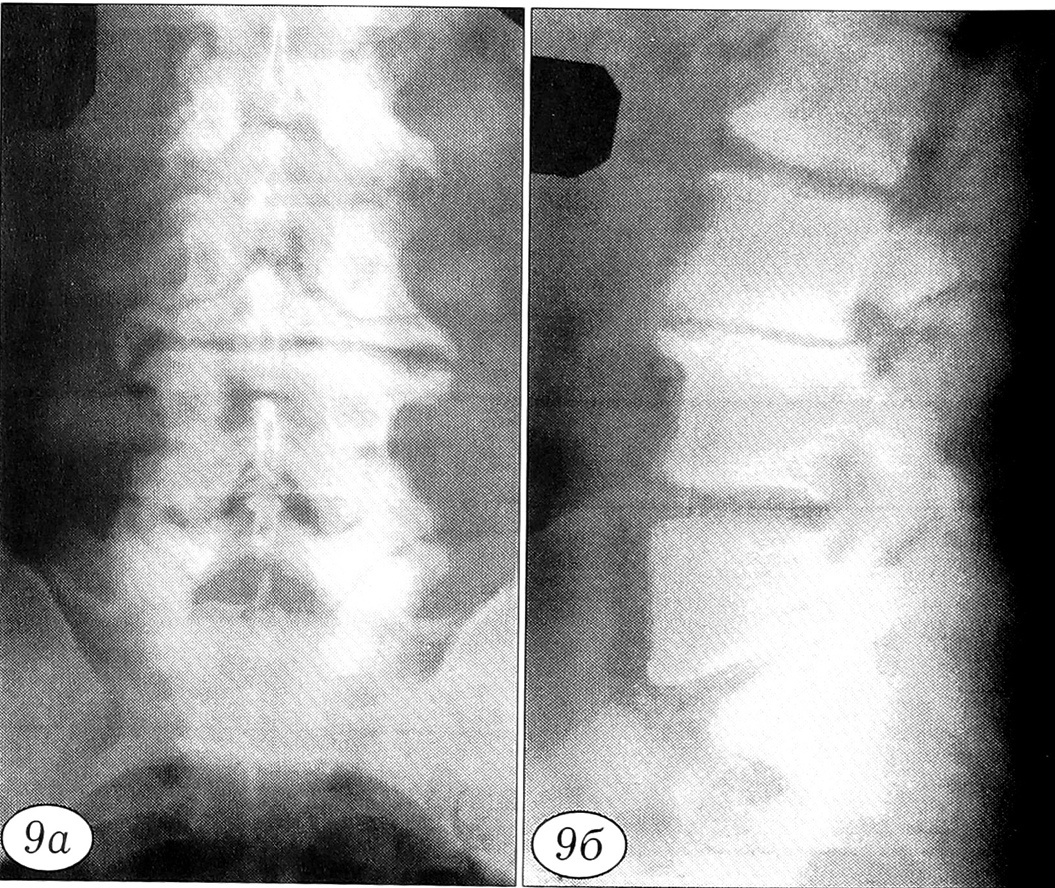

Рис. 2. Боковые рентгенограммы поясничного отдела позвоночника больного К.: формирование структурных изменений при остеохондропатии позвоночника. a — нарушение контуров замыкательных пластинок тел L2-5 позвонков в 8-летнем возрасте; б — грыжи Шморля, остеопороз тела L2 позвонка, снижение высоты L2~3 межпозвонкового диска в 13-летнем возрасте.

Рис. 9. Рентгенограммы (а — прямая, б — боковая) поясничного отдела позвоночника больного А. 49 лет. Исход остеохондроза: фиброз L3-4 диска, дегенеративный спондилолистез L3 позвонка, остеофиты, компенсаторная перестройка губчатой кости тел L3, L4 позвонков.